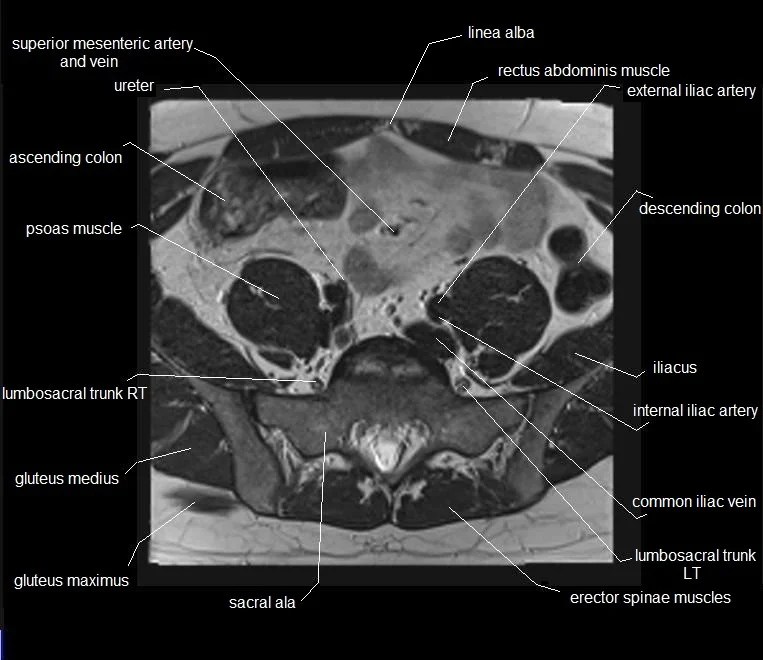

MRI Pelvis Muscle Anatomy

Diagram of Axial MRI of pelvis and gluteus muscle group Quizlet Mri Anatomy Pelvic Muscles Use the mouse scroll wheel to move the images up and. Adductors, flexors, abductors, extensors, and external rotators (fig 1). This article reviews normal male pelvic floor anatomy and how it differs from the female pelvis; This mri male pelvis axial cross sectional anatomy tool is absolutely free to use. Dynamic pelvic floor mri provides detailed pictures of the pelvic. Mri Anatomy Pelvic Muscles.